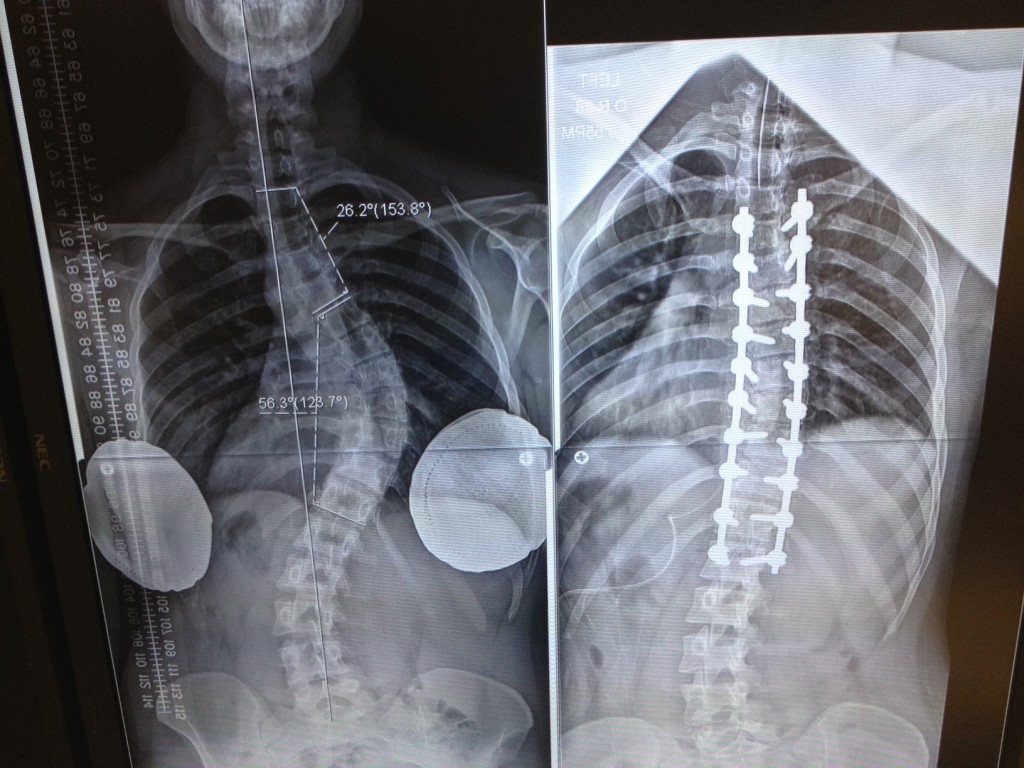

Scoliosis

I have lived with back problems since I was diagnosed with scoliosis at the age of 18. Having had six back operations prior to coming to HSS, needless to say I was desperate to find someone to relief this horrific pain that I have lived with for over twenty years. Into my life comes Dr. Matthew Cunningham, a brilliant doctor, who has not only relieved me finally of my debilitating pain but treated me with the most amazing care. Dr. Cunningham made me feel like I was his only patient, listening to me, helping me understand my body and what would relieve my pain. His kindness, empathy and fabulous sense of humor are amazing especially so in this day and age. I have been to many “world renowned specialist” and have never experienced the type of excellent care that I received from Dr. Cunningham. HSS should be commended for having a Doctor as Dr. Cunningham on their staff. And not surprisingly Dr. Cunningham’s Administrative Assistant, Tina Miller, is one of the kindest, compassionate and highly efficient assistants I have ever met as is Dr. Cunningham’s nurse, Cynthia. If you have back pain, you owe it to yourself to have the privilege of being treated by Dr. Cunningham and his team at a fabulous hospital, Hospital for Special Surgery. I should know since I have had five operations at HSS. Dr. Cunningham has given me a new lease on life. I will always be so grateful for the amazing care, professionalism and unheard of empathy that this brilliant Dr. Cunningham has given to me. A gift I will never forget.